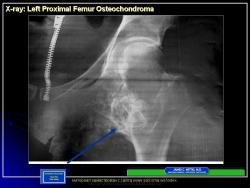

Иллюстрации из литературных источников.

14.N.Slayd15.JPG15.N.Slayd16.JPG16.N.Slayd17.JPG17.N.Slayd18.JPG18.N.Slayd19.JPG19.N.Slayd20.JPG1.1.Slayd20.JPG2.2.Slayd21.JPG3.3.Slayd22.JPG210.OH_.Slayd25.JPG